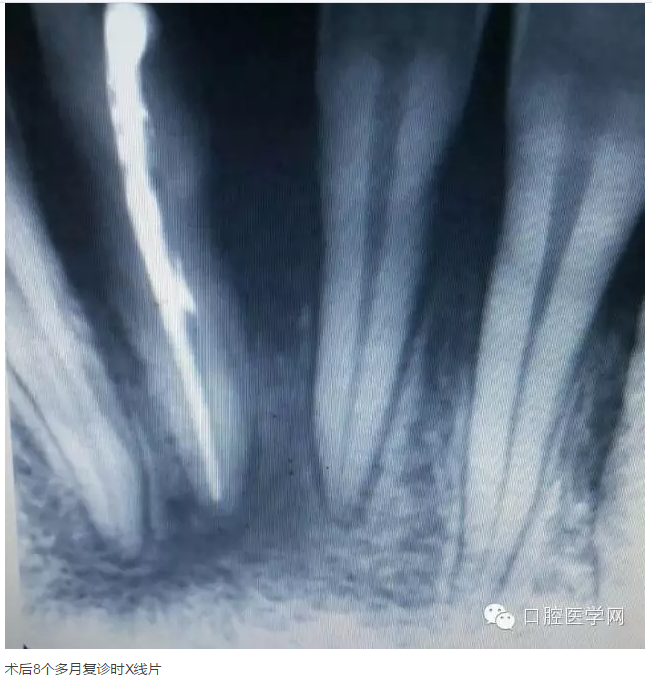

下面是一例 今年年初治療的下前牙根尖囊腫病例,患者因故未能按時復診,最近才來。